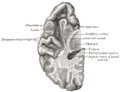

| المخ: مهاد Thalamus | ||

| مقطع صورة رنين مغناطيسي لمخ بشري, المهاد مبين فيه. | ||

المهاد Thalamus (من اليونانية θάλαμος = المهد أو المخدع, غرفة) هو زوج وجزء متماثل في المخ. وتشكل الجزء الرئيسي من diencephalon.